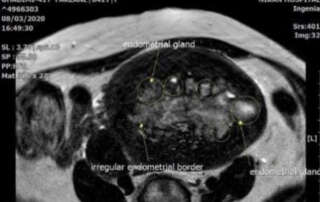

Extra-ordinary High Cancer antigen 125 (CA-125) level in a 41 year-old patient with adenomyosis

DOI: 10.36205/trocar3.2021003